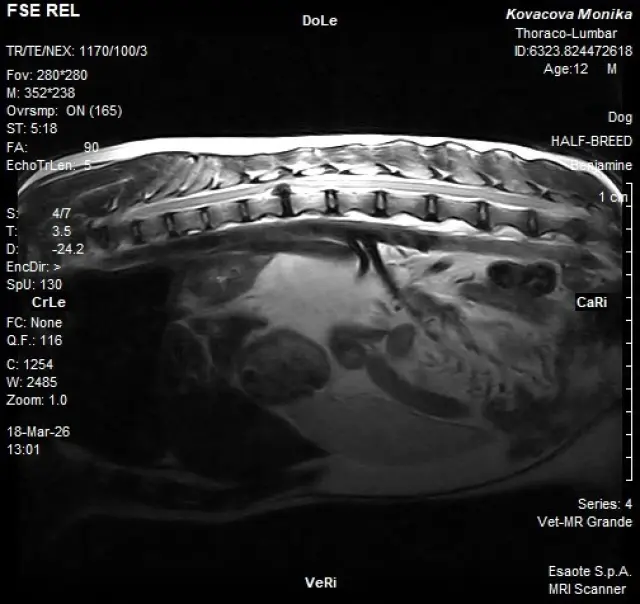

Toto však už nie je možné. 18. marec 2026 sa stal najhorším dňom tohto roku. Nádej, že má Benji iba narazený chrbát a dostaneme sa z toho pomocou medikácie, skončila. MRI vyšetrenie potvrdilo veľký nález – extrúziu medzistavcovej platničky.

Ide o závažný stupeň poškodenia platničky, pri ktorom dochádza k pretrhnutiu jej vonkajšieho prstenca a následnému úniku rôsolovitého jadra do miechového kanála. Jadro je už úplne mimo pôvodného priestoru, čo často spôsobuje silný útlak nervových štruktúr alebo miechy.